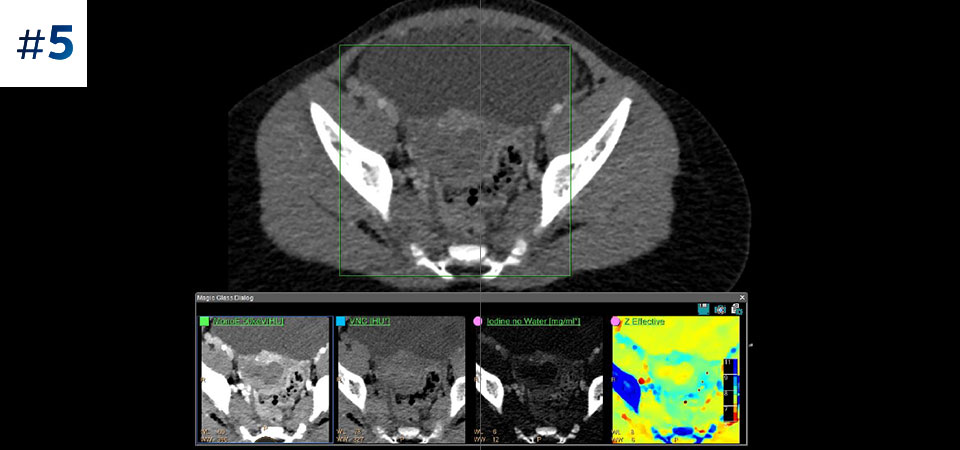

Nuestro CT con detección espectral de Philips, nos permite adquirir datos convencionales y espectrales en una sola exploración, sin cambios en nuestro flujo de trabajo actual.

Observe las diferencias entre un detector espectral CT y un CT Convencional

Aprenda sobre las ventajas del detector espectral CT